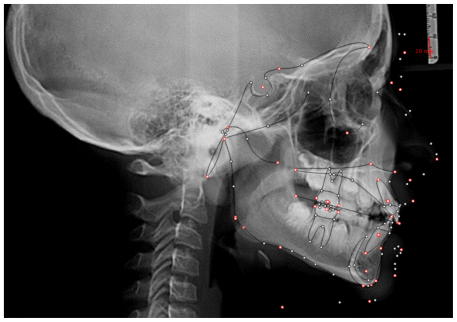

The patient was a young female presenting with a Class III dento-skeletal malocclusion, which was treated using the AMCOP® TC appliance. A comprehensive diagnostic protocol was carried out both before and after treatment, including orthopantomography (Figure 2–3), postero-anterior teleradiography (Figures 4, 5), latero-lateral cephalometric radiography (Figures 6, 7), cephalometric analysis (Tables 1, 2), as well as extraoral (Figures 8, 9) and intraoral photographs (Figures 10, 11). The extraoral examination revealed an edge-to-edge incisal relationship and the presence of a midline diastema. Pre-treatment cephalometric analysis (Deltadent® Lana, Bolzano, Italy) confirmed the diagnosis of a skeletal Class III malocclusion. The treatment plan involved the use of the AMCOP® TC appliance. The patient was instructed to wear the device for two hours in the afternoon and throughout the night for the first six months, followed by nighttime use only for an additional six months. Upon completion of the treatment, the patient achieved a Class I occlusion, with correction of both overjet and overbite. Additionally, the device facilitated tongue re-education and contributed to the postural realignment of the first cervical vertebra.

Lateral cephalograms were analyzed at T0 and T1 using DeltaDent® software to measure treatment outcomes.